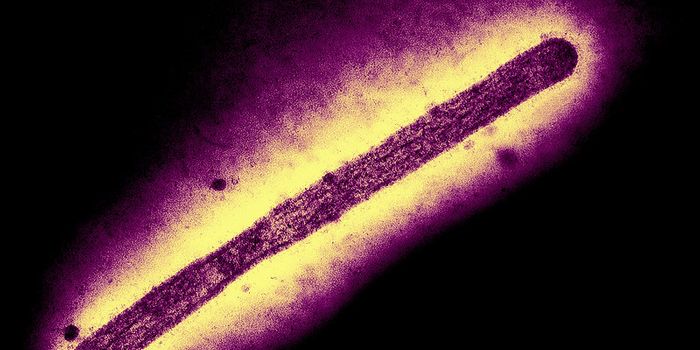

APR 27, 2025MicrobiologyThe SARS-CoV-2 virus that causes COVID-19 emerged to cause millions of deaths and sicken billions of people...